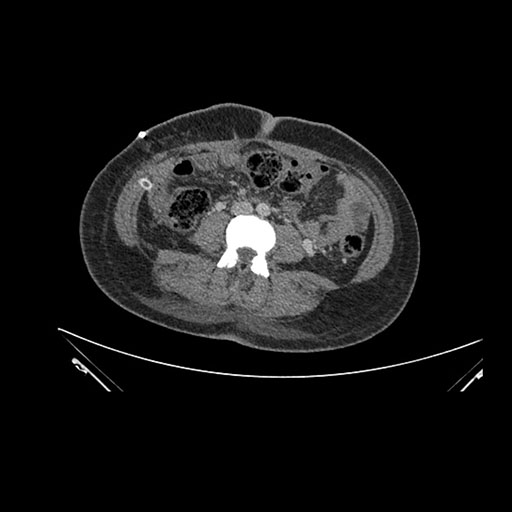

Imaging Analysis

Look through the patient's CT scan to identify any areas of concern for the necessary procedure.

Axial Venous

Based on initial findings, which issue(s) would you be most concerned about?